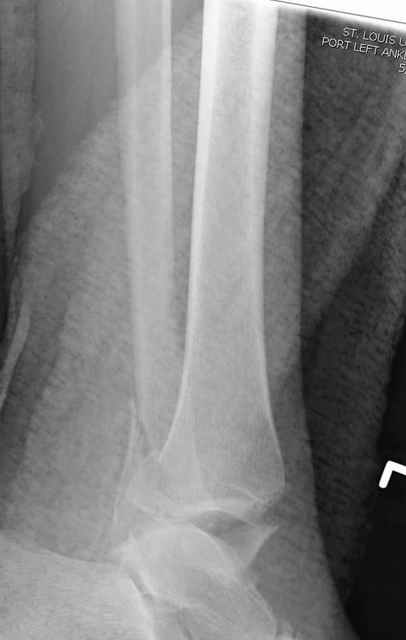

Традиционная техники АО, открытая, с точной репозицией суставной поверхности и жесткой фиксацией, из-за серёзных осложнений, которые

заканчивались ампутацией, уходит в прошлое.

Техника сегодня более щадящая, временные несложные аппараты наружной фиксации: Spanning 2 pin ExFix, Traveling traction для лигаментотаксиса, иначе сокращенные мягкие ткани невозможно восстановить позже.

За последнее 10-12 лет после стабилизации малоберцовой кости, стали применять более усовершенный, сложный, хорошо вам известный метод

Илизарова (кстати наряду с тибиал плато, пилон является одним из показанием по применению аппарата Илизарова при травмах) или Hybrid

Fixator, из минимальных доступов комбинированный метод для восстановления суставной поверхности-фиксация каннулированными

шурупами, создания жесткой системы фиксации до сращения перелома, защита от вальгусной деформации и на место образовавщегося метафизарного дефекта- костная пластика ауто костью или его

синтетические заменители, это сегодняшная тактика лечения.